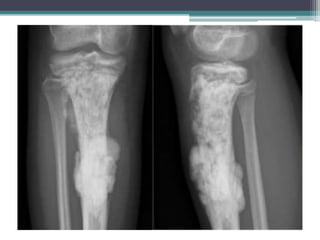

OSTEOSARCOMA Hechos ycifras • Tumor óseo maligno primario mas común. • Segundo tumor óseo primario más común y es altamente maligno. Es más común entre las personas de 10 a 25 años, aunque puede ocurrir a cualquier edad. • 50% alrededor de la rodilla (fémur distal con más frecuencia que la tibia proximal) o en otros huesos largos (como el húmero proximal), en particular en la zona metafiso diafisaria, y puede metastatizar, por lo general a los pulmones o en otros huesos. • Presentación: dolor, masa, fractura patológica. • La esclerosis está presente, ya sea en la formación de tumores de hueso nuevo o esclerosis reactiva.

• Las radiografíassimples típicamente revelan lesiones con patrón apolillado o permeativo de la zona de transición con destrucción cortical irregular y una reacción perióstica interrumpida con extensión de tejidos blandos. • Una reacción perióstica conocida como “triángulo de Codman” aparece cuando el tumor eleva el periostio del hueso subyacente. • La extensión cortical de tejido blando puede producir espículas radiadas de hueso llamado apariencia en “rayo de sol”.

• El osteosarcomamaligno produce osteoide (hueso inmaduro) de las células óseas tumorales. • La formación de hueso explica las imágenes radiográficas. • Cuando la matriz tumoral ósea es deficiente, el osteosarcoma puede ser del subtipo telangiectasico (que algunas veces puede imitar un quiste óseo aneurismático), o el diagnóstico diferencial incluye el sarcoma de Ewing o linfoma, especialmente cuando una gran masa de tejido blando está presente. • En pacientes de edad avanzada, el diagnóstico diferencial también puede ser condrosarcoma.

• Generalmente sedesarrolla alrededor de la rodilla • El dolor y la hinchazón son los síntomas habituales. • Los hallazgos en los estudios de imagen varían y pueden incluir características escleróticas y / o líticas. • El diagnóstico requiere una biopsia. • Se necesitan radiografías de tórax y TC para detectar metástasis pulmonares y una gammagrafía ósea para detectar metástasis óseas.